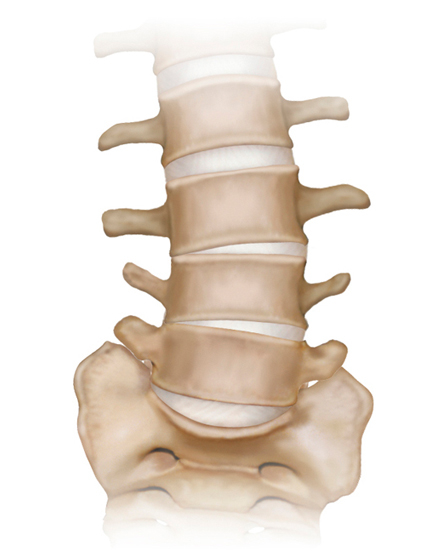

低侵襲脊椎側方固定術 XLIF (エックスリフ)、OLIF(オーリフ)

適応となる疾患:腰椎椎間板ヘルニア、腰部脊柱管狭窄症、腰椎変性すべり症、腰椎変性側弯症など

日本では2013年から承認されている低侵襲な脊椎側方固定術です。この手術は、トレーニングを受けた医師だけが実施できるため、全国でも限られた医療機関でのみ受けられます。当センターの日方医師は資格を有しているため実施可能です。この手術の最大の利点は脊髄神経を直接触らないで神経を圧迫から解除することにあります。側腹部に約5cmの皮膚切開により、下図のように神経機能を電気モニタリングで随時確認し重要な神経を避けながら椎間板内に人工骨を移植します。その後、腰部から固定術を行います。翌日から起立・歩行が許可され、入院期間は通常10~14日程度になります。